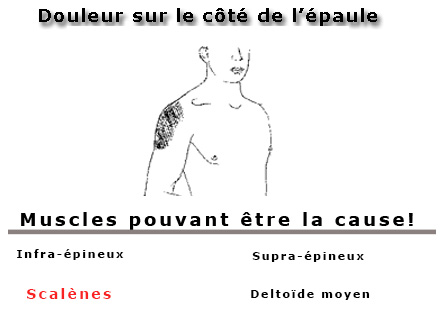

- Douleur à l'épaule

- Douleurs aux épaules